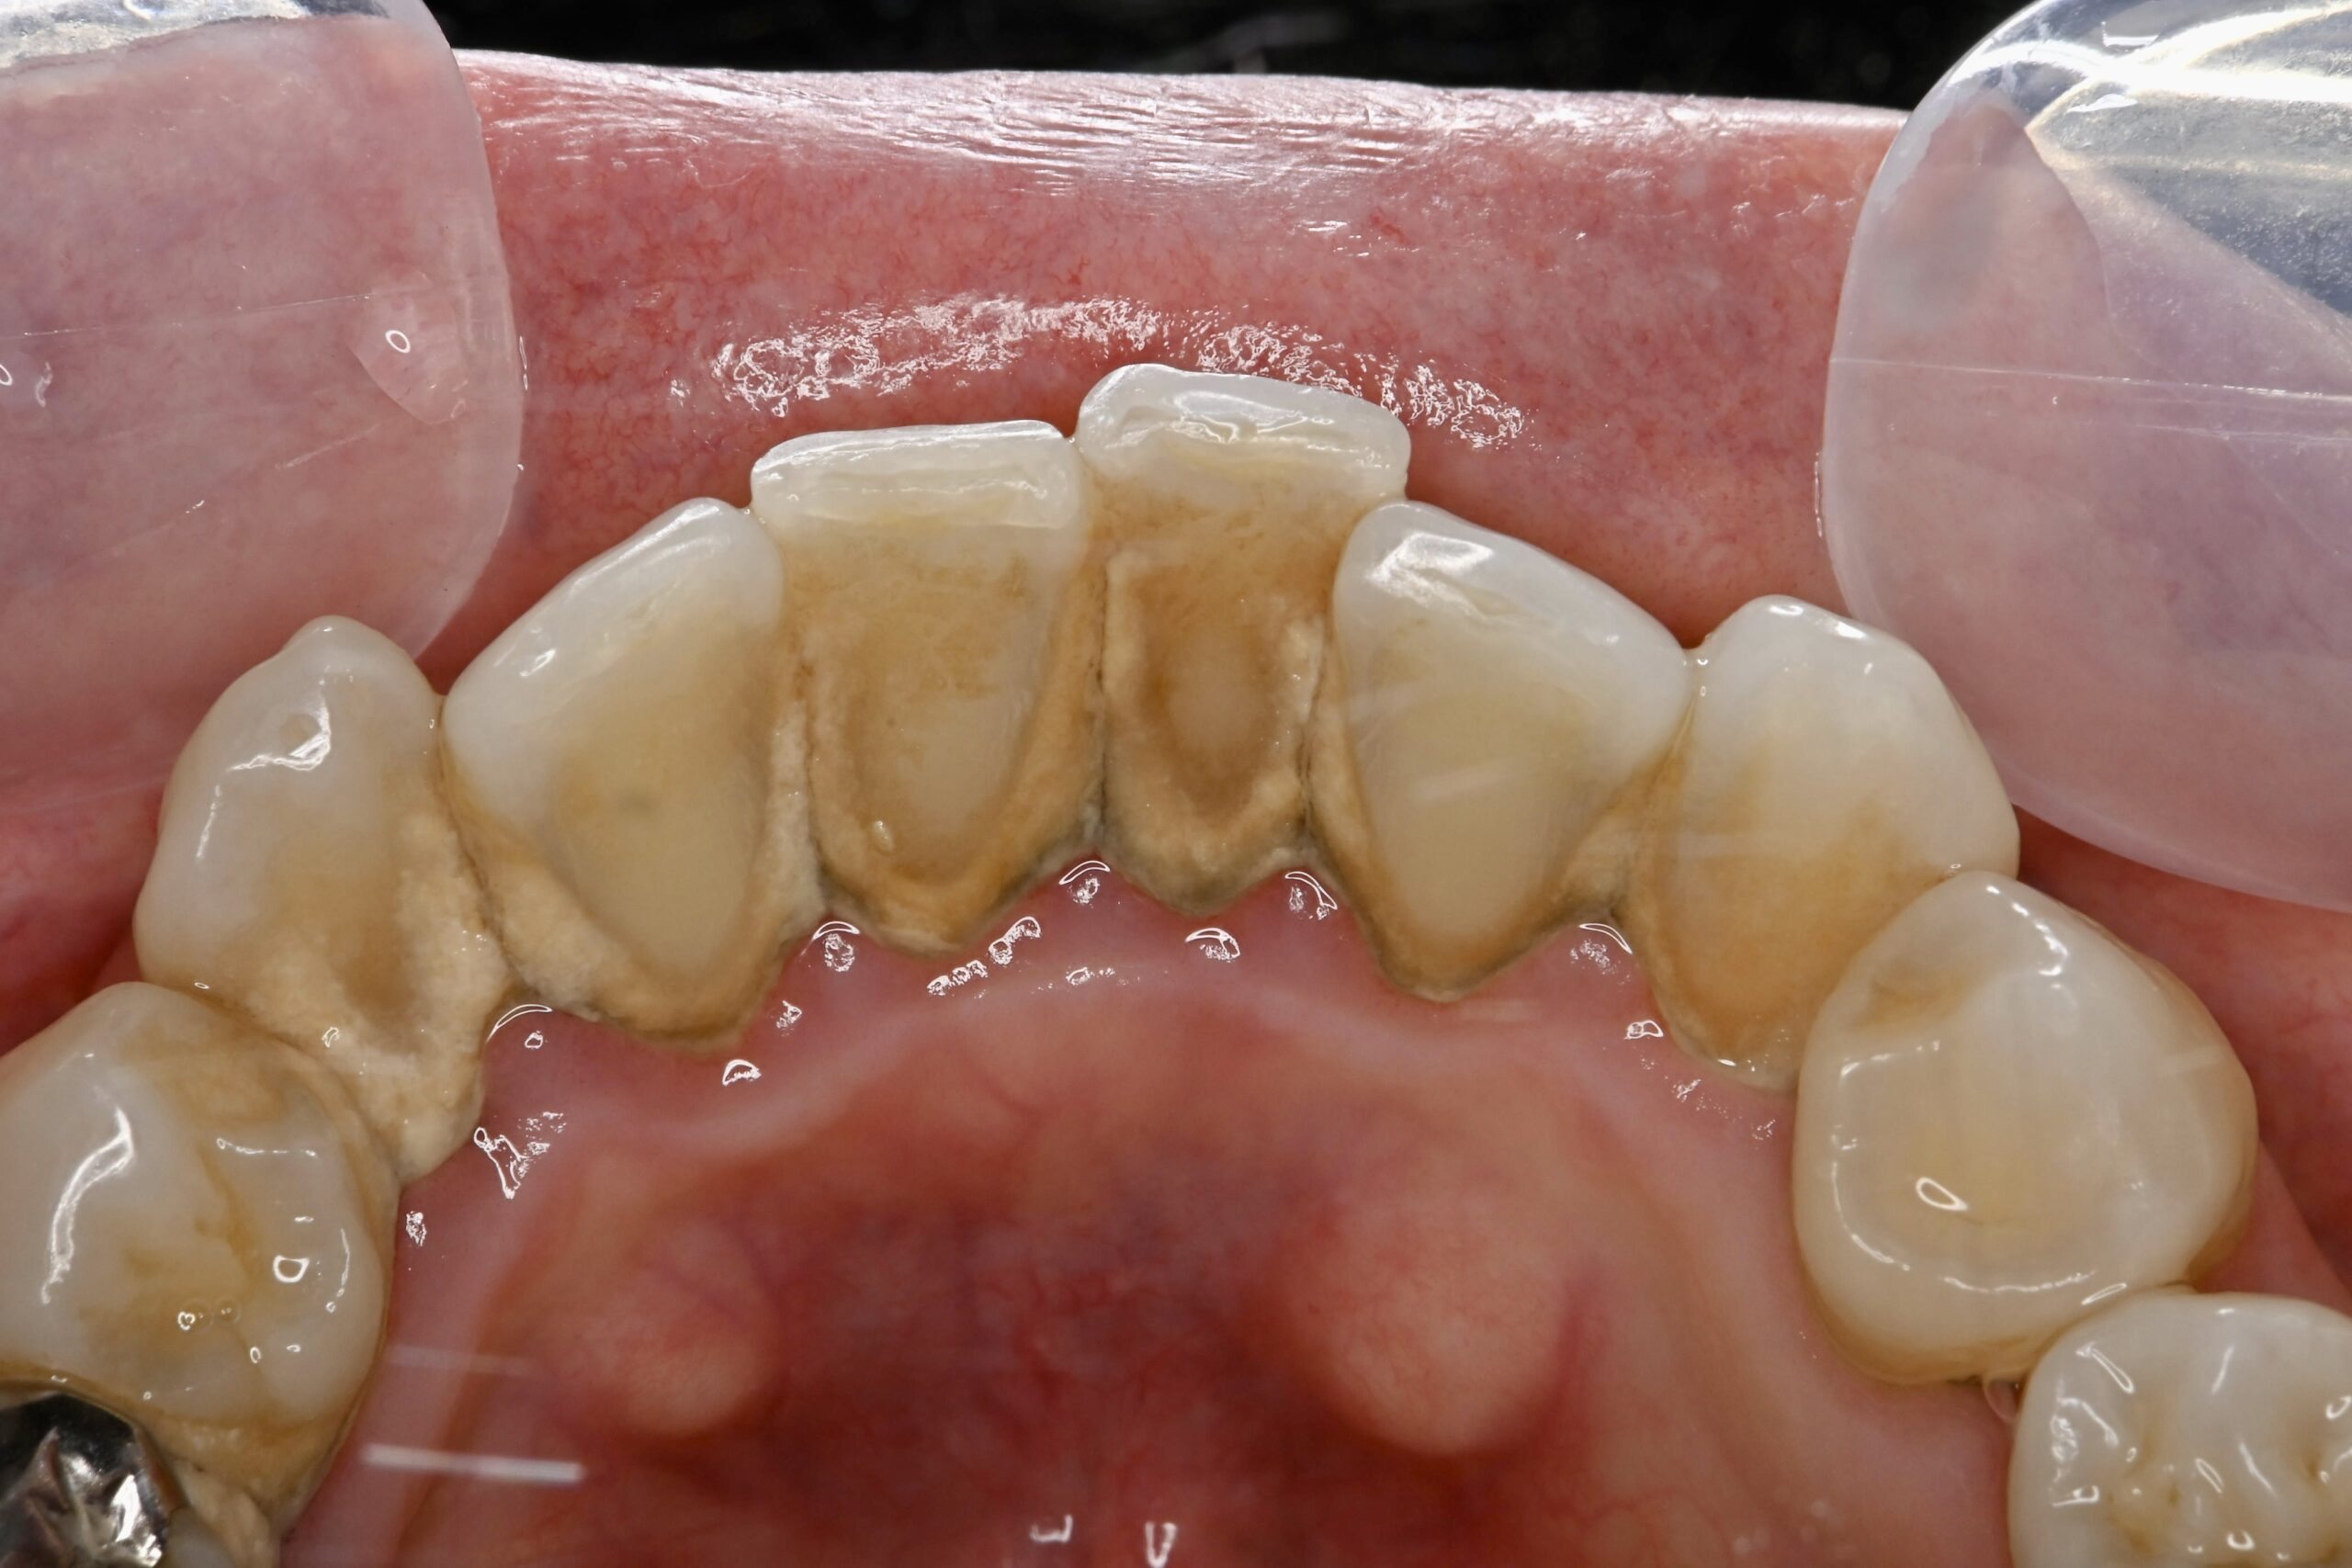

初診時

ブラッシング指導・スケーリング後

| 主訴 | 歯茎から出血する 歯科を受診するのは5年ぶり |

| 治療内容 | ブラッシング指導 歯肉縁上スケーリング(歯石の除去) 歯面清掃 |

| 治療期間 | 1ヶ月 |

| 費用 | 保険治療 |

| リスク・副作用 | 歯肉が引き締まることによる歯肉退縮 歯肉退縮による審美不良(歯が長く見える)や知覚過敏症状の発生 |